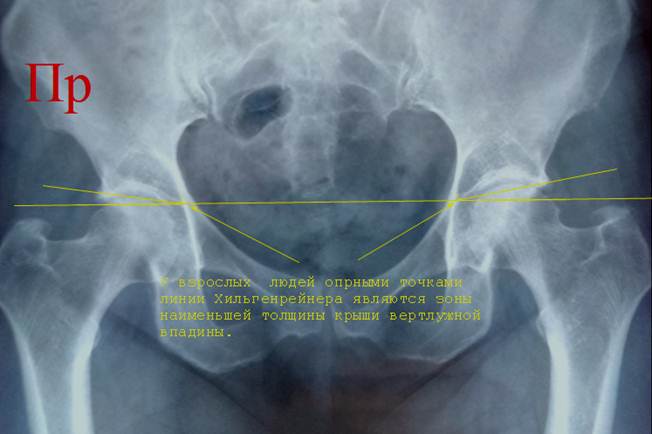

Снимок

таза взрослого человека. Нижние края тел

подвздошных костей определяются зонами истончения крыши вертлужной впадины. Из

этих же зон начинаются линии

ацетабулярного угла.